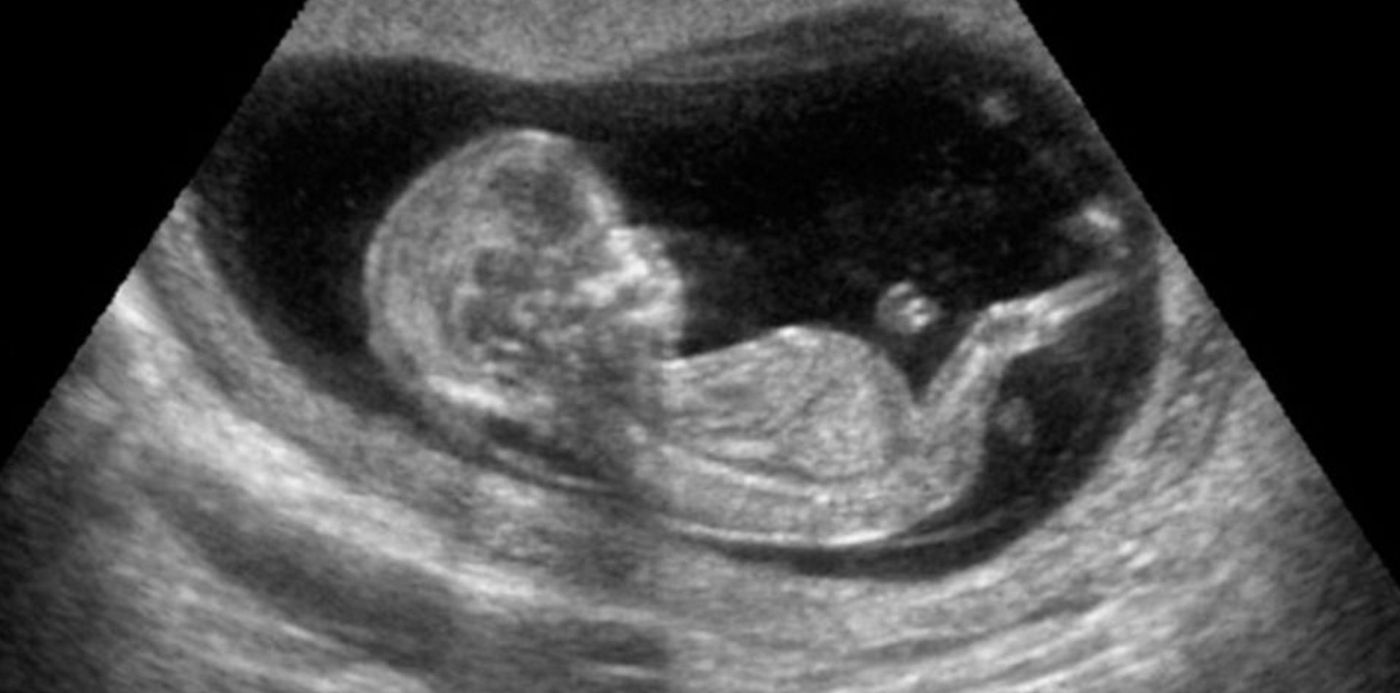

Alerta embarazadas: se prohibió el uso de un ecógrafo en todo el país

La Administración Nacional de Medicamentos, Alimentos y Tecnología Médica ordenó sacar de circulación este producto tras una denuncia por robo en Tres de Febrero. Así se publicó en el Boletín Oficial del Gobierno Nacional.

La Administración Nacional de Medicamentos, Alimentos y Tecnología Médica prohibió el uso y comercialización en todo el país de ecógrafo portátil y sus accesorios. Así se decidió tras una denuncia.

En base a esto se publicó la resolución en el Boletín Oficial: "Prohíbese el uso y distribución en todo el territorio nacional del siguiente producto médico y sus accesorios: 'Ecógrafo portátil Sonosite Micromaxx, marca Sonosite, Serie 038ZQG'; 'Transductor convexo C60, marca Sonosite, Serie 03VW61'; -'Transductor P17, marca Sonosite, Serie 03MXCW', por los fundamentos expuestos en el Considerando".